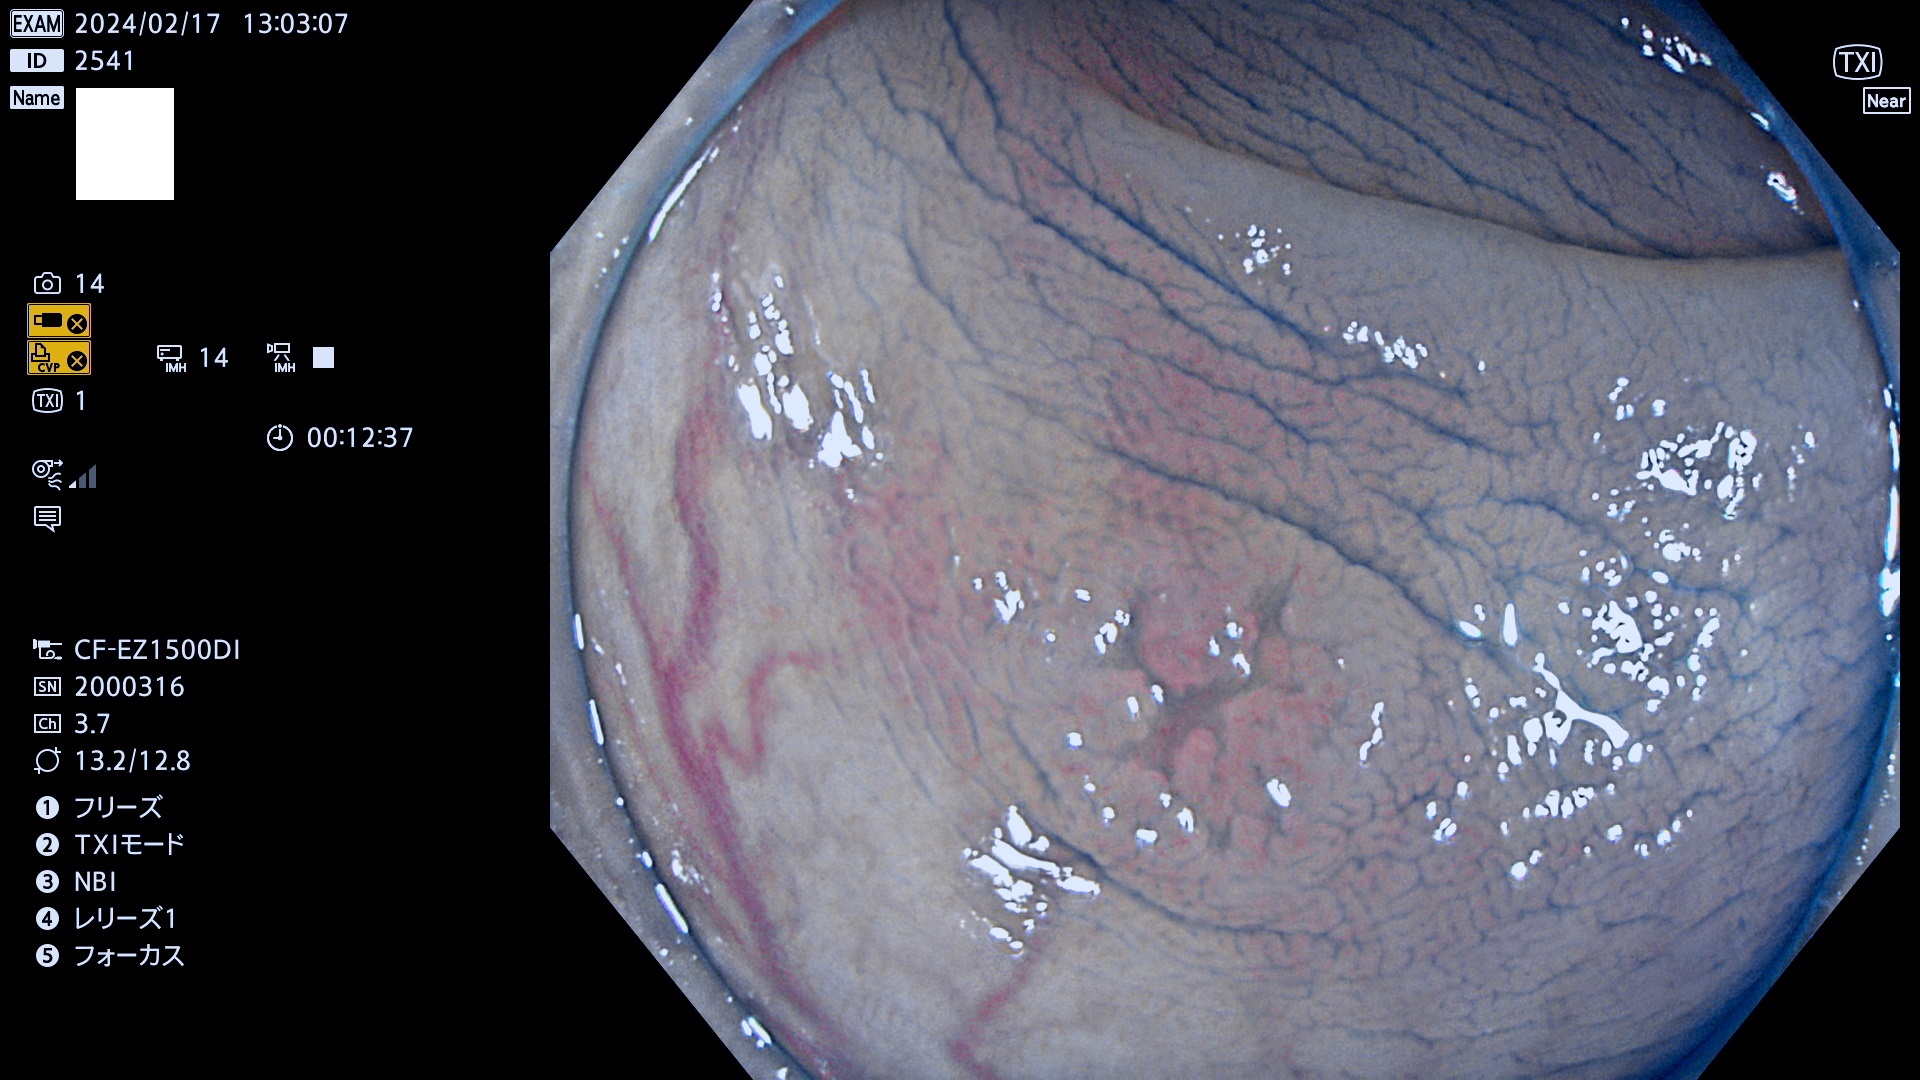

表面型腺腫(Flat Adenoma)の中で、完全に平坦な物をUb、陥凹している物をUcと呼びます。平坦隆起型(Ua)よりも、発見が難しく危険な病変です。

毎週の検査(木・金・土・日)に発見されたUb、Uc型・腺腫を、その週の日曜の夜にUPし1週間、提示します。

抽出の対象期間 2024年2月15日(木)〜2月18(日)の4日間(40件の検査)10件 (10/40=25%)